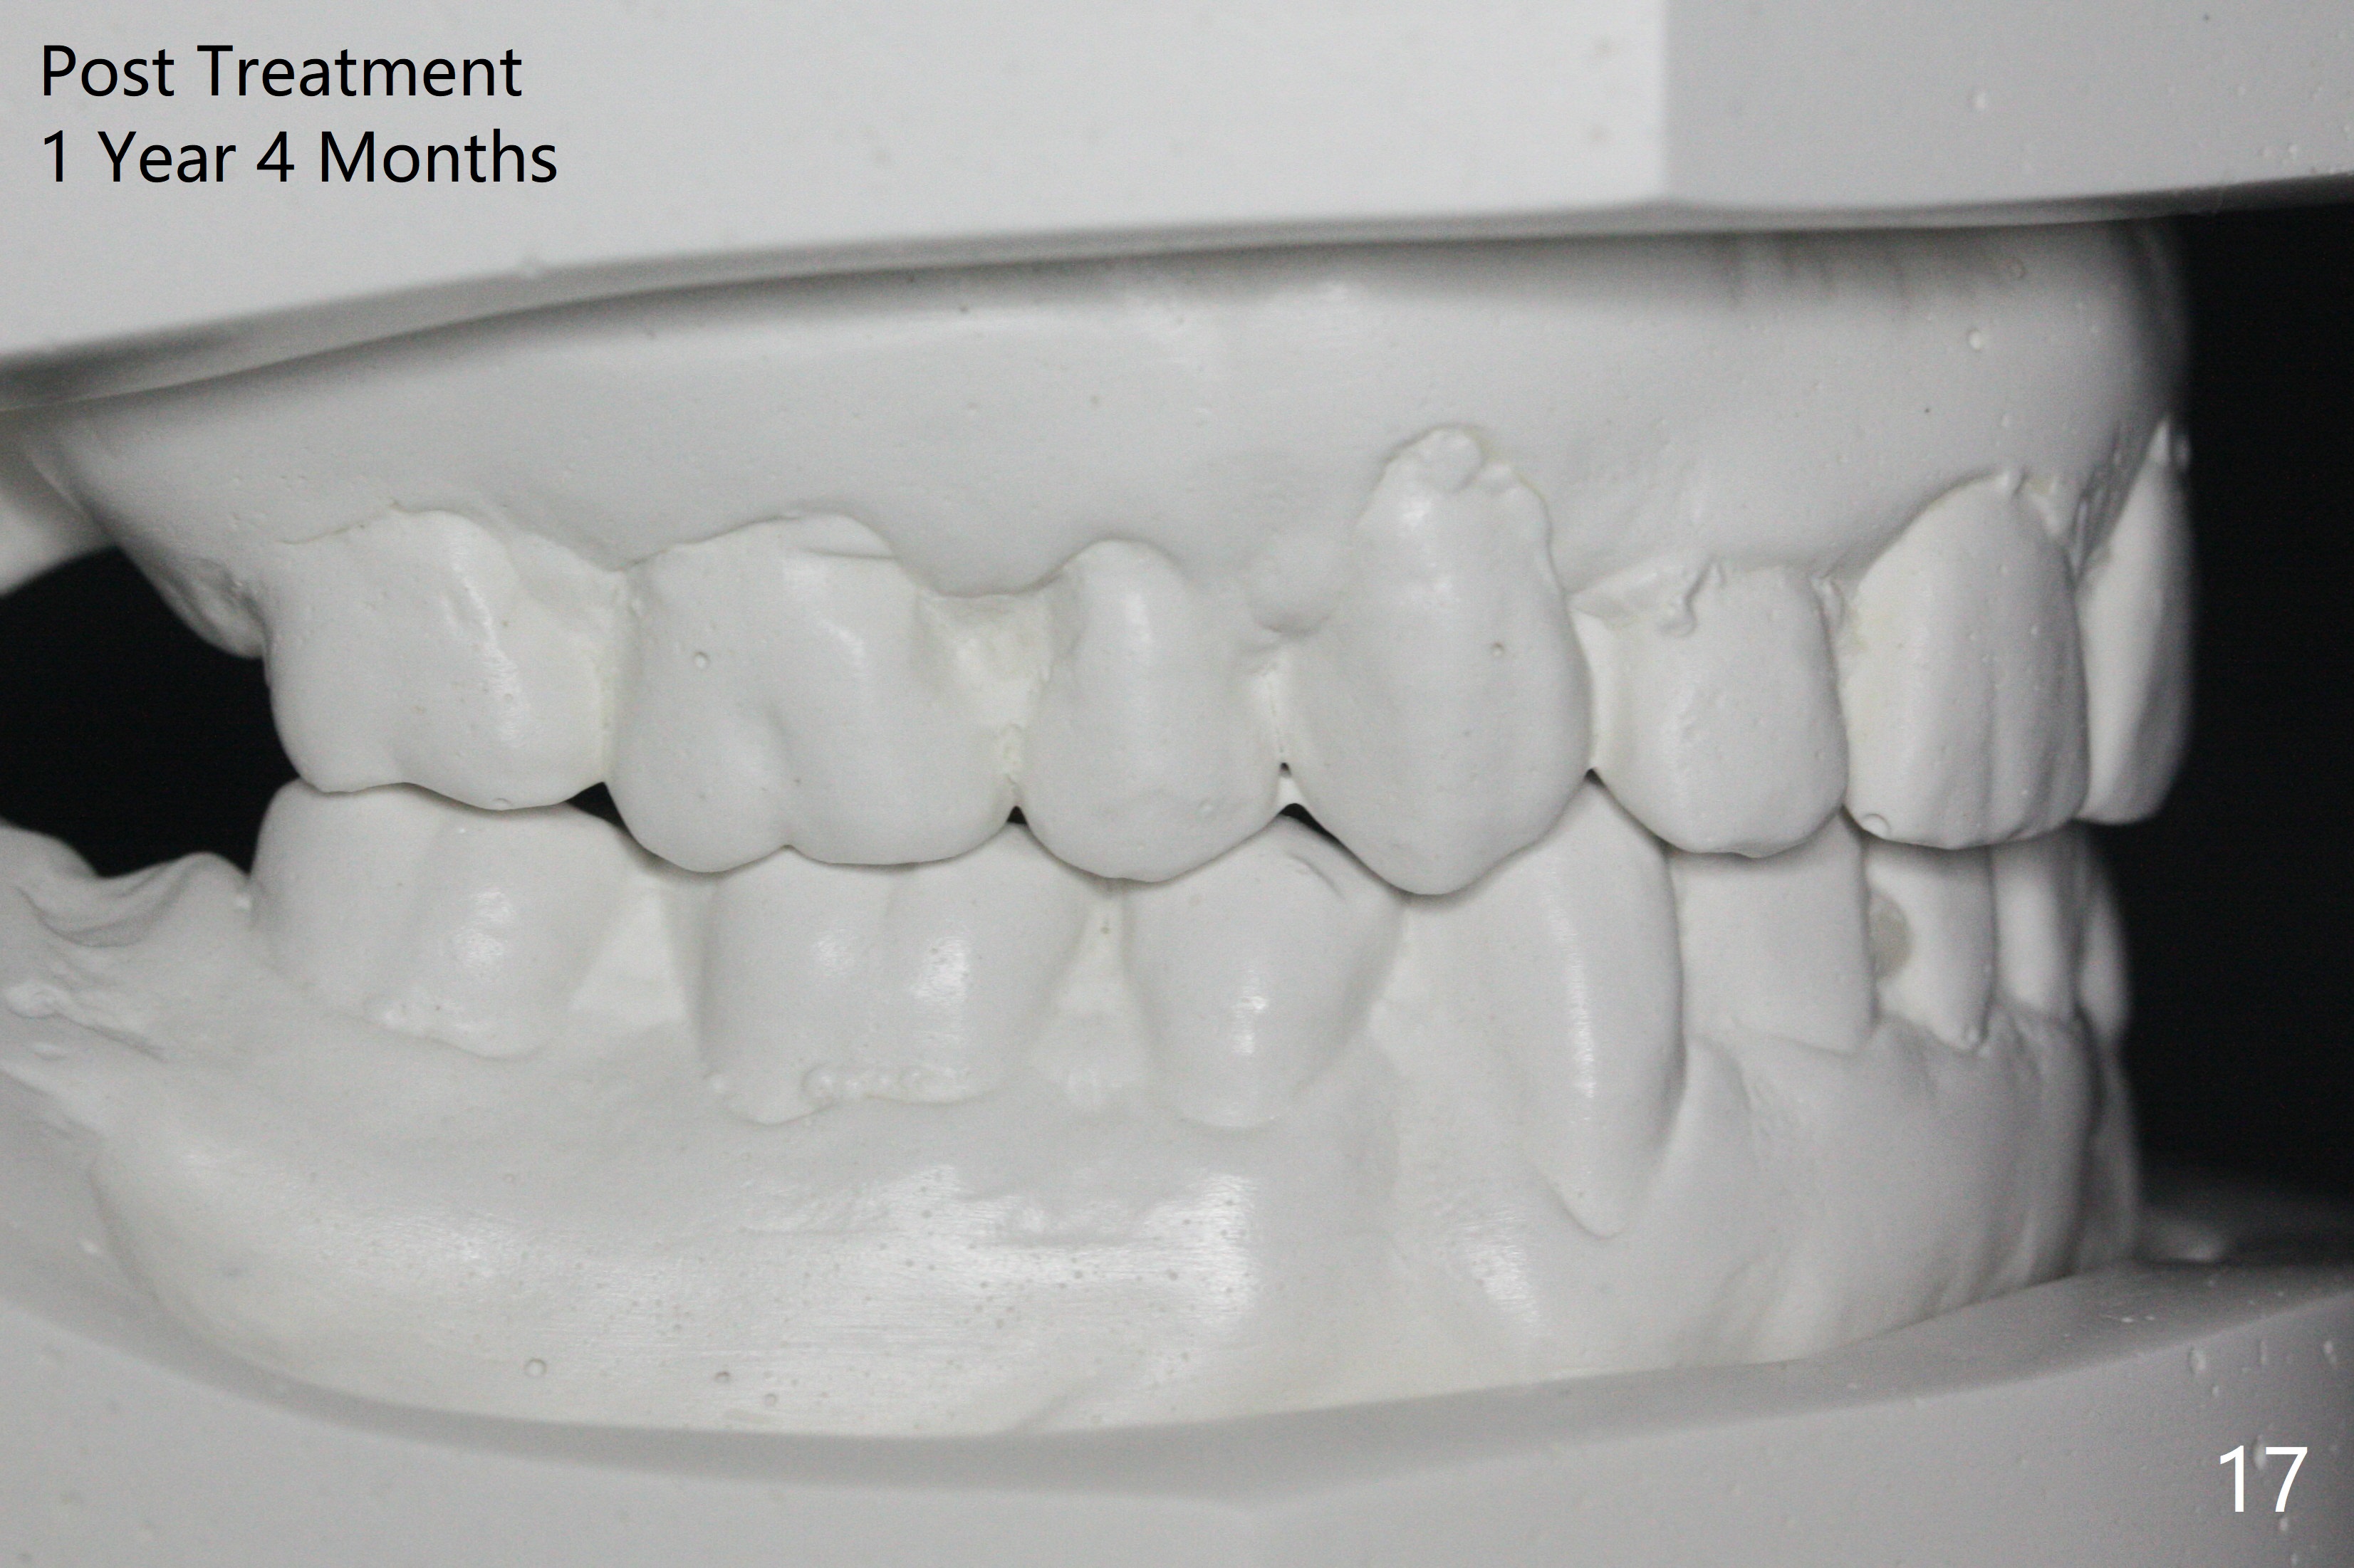

Enough Space For Crowding After Extraction? A 47-year-old man requests orthodontic treatment following SRP in other office (Fig.1-11). For severe crowding and midline shifting, extraction of four of the 1st bicuspids is imminent. Is it enough? To answer the question, model surgery is performed (Fig.12-16). 1st visit: periodontal maintenance, orthodontic consent (emphasizing oral hygiene) extract 4s and possibly L8s and separators. The beauty of this vist is that after local anesthesia and extraction including L8s, it is painless and easy to remove calculus from the proximal surfaces of the neighboring teeth. It is much easier to place separators after extraction. It is expected that there is no gingival erythema when the patient returns for bracketing. Take photos of UR3, similar to Fig.3. Molar banding is also anticipated to be easy with separator placement after extraction. Return to Ortho Cases Xin Wei, DDS, PhD, MS 1st edition 11/23/2017, last revision 04/28/2019